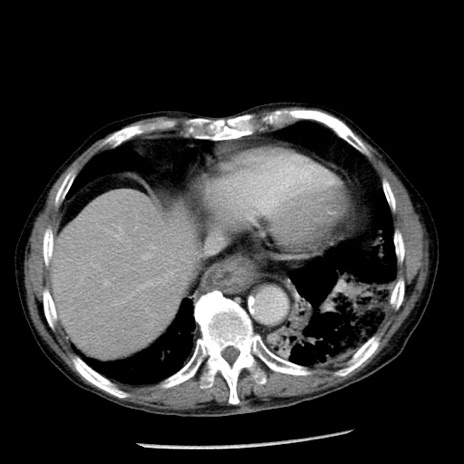

症例26(横断像)

【症例】80歳代男性

【主訴】嘔吐

【現病歴】昨晩2回嘔吐あり、今朝になっても嘔吐あり。来院。

【既往歴】胃潰瘍

【身体所見】意識清明、BT 37.6℃、BP 166/95mmHg、HR 100bpm、SpO2 97%、腹部:平坦・軟、腸蠕動音聴取良好、圧痛なし。

【データ】WBC 21900、CRP 1.46